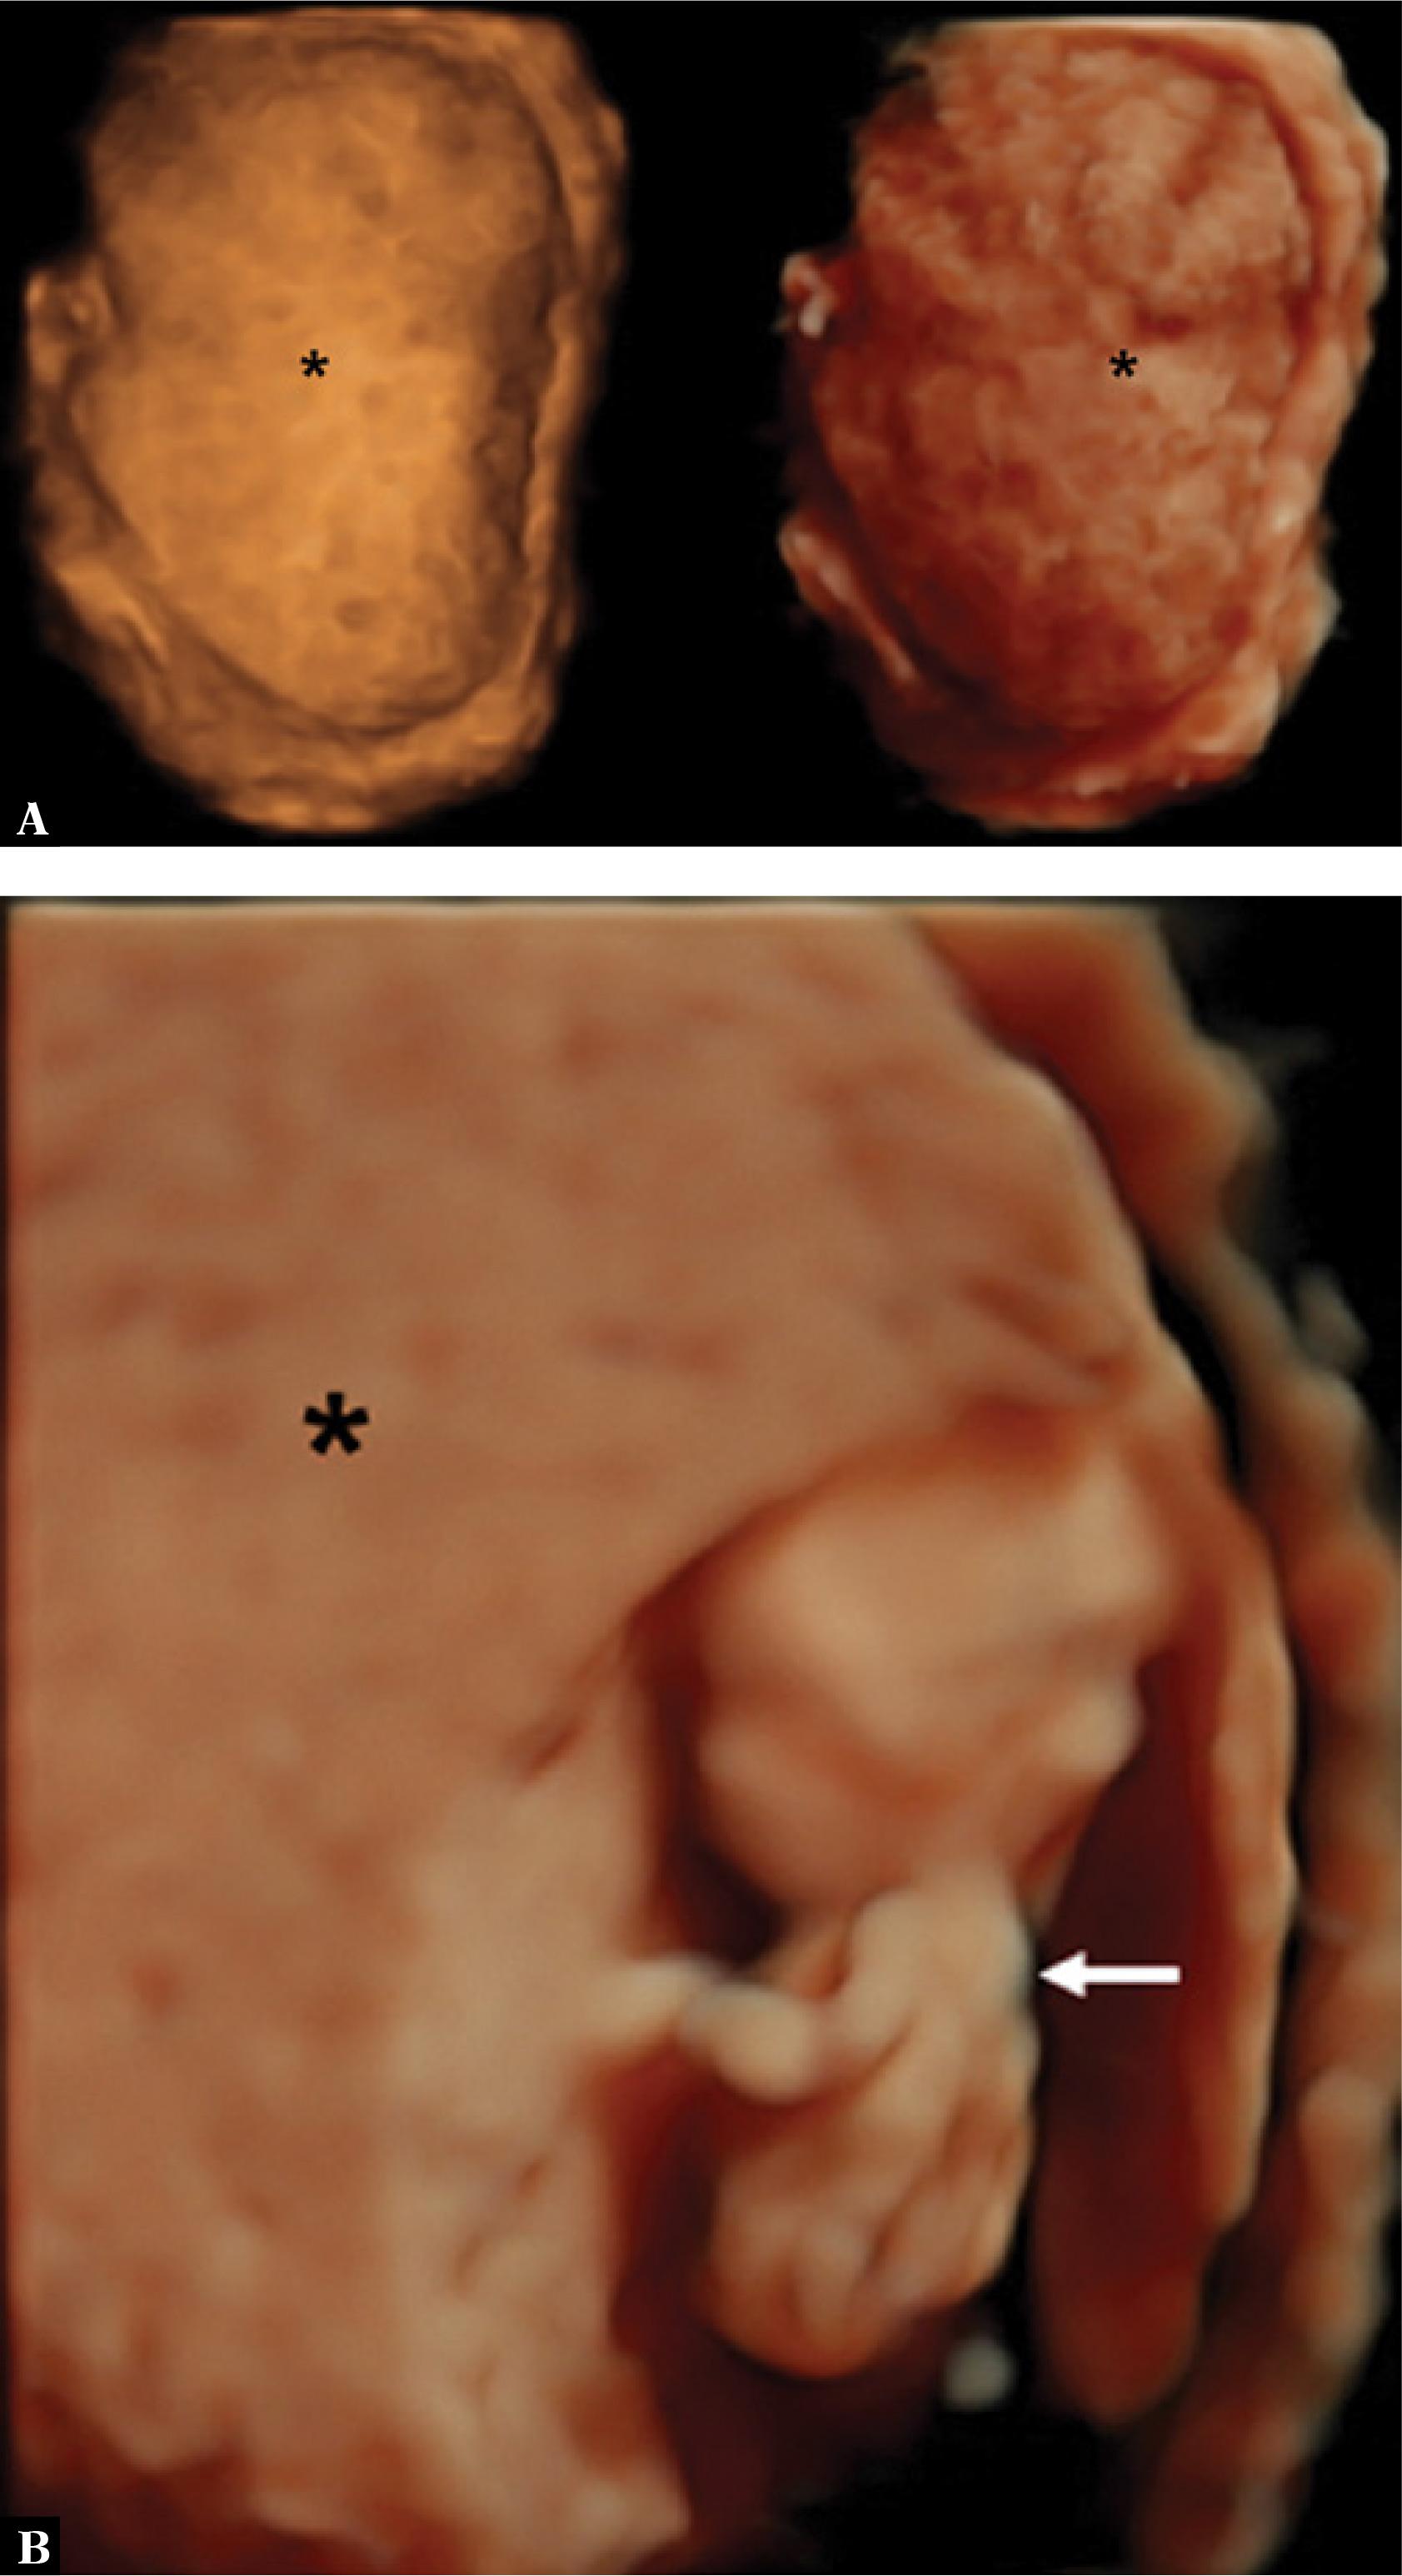

A three-dimensional (3D) ultrasound in HDlive rendering mode showed a realistic image of a fetus coexisting with a hydatidiform mole (Fig. 2). Magnetic resonance imaging (MRI) was performed to better determine the relationship between the living fetus and the hydatidiform mole. T1- and T2-weighted MRI images showed an enlarged uterus filled with amorphous heterogeneous material coexisting with a live fetus (Fig. 3), along with a distinct junction between the myometrium and the molar tissue but without evidence of myometrial invasion. These findings were compatible with the diagnosis of a twin pregnancy with a complete hydatidiform mole and a coexisting live fetus.

Fig. 2

A. A three-dimensional (3D) ultrasound using HDlive rendering mode shows a molar pregnancy (*). B. A 3D ultrasound with HDlive showing a fetus with a gestational age of 14 weeks (arrow) and molar degeneration (*)